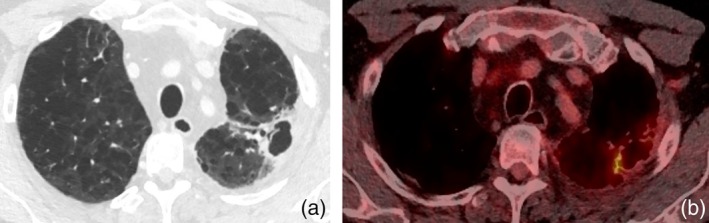

矽肺病是一种重要的职业病,由吸入二氧化硅引起,可导致肺部炎症和纤维化。矽肺可误诊为恶性疾病,因为两者在FDG-PET成像上均可表现为高代谢病变。本病例系列描述了3例基于FDG-PET检查结果怀疑有原发性肺恶性肿瘤的患者,但发现有肺矽肺病。通过这个系列,我们展示了组织学检查如何区分矽肺和恶性肿瘤,并提供建议,以帮助临床医生区分这两种疾病。

Silicosis, an important occupational disease, is caused by inhalation of silicon dioxide and can lead to pulmonary inflammation and fibrosis. Silicosis can be misdiagnosed for malignant disease, as both can present with hypermetabolic lesions on FDG-PET imaging. This case series describes three patients who were suspected to have a primary lung malignancy based on FDG-PET findings, but were found to have pulmonary silicosis. With this series, we demonstrate how histologic examination can differentiate between silicosis and malignancy and provide suggestions to help clinicians differentiate between these two illnesses.